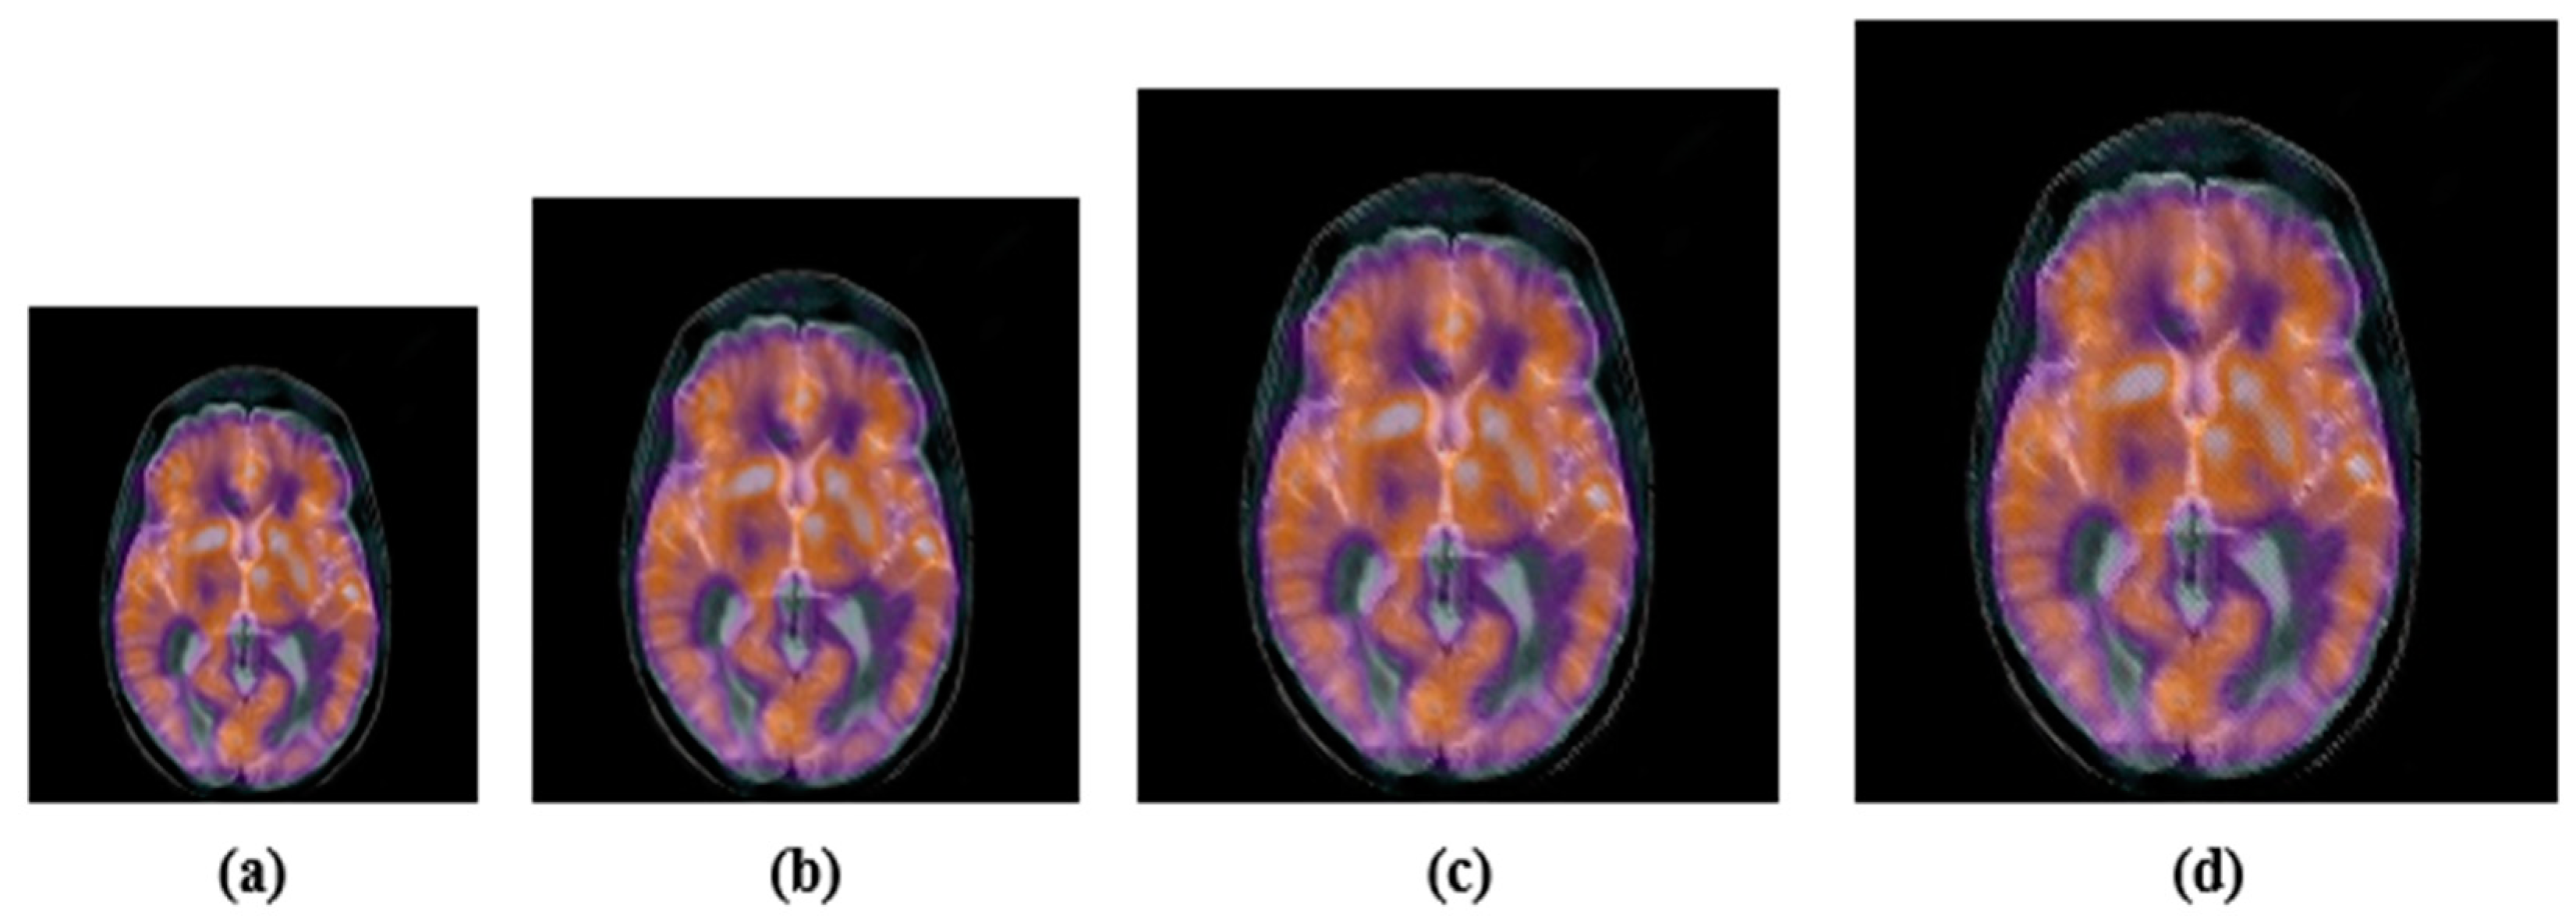

4.2.1. Common Signal Processing Attacks

4.2.2. Geometric Attacks